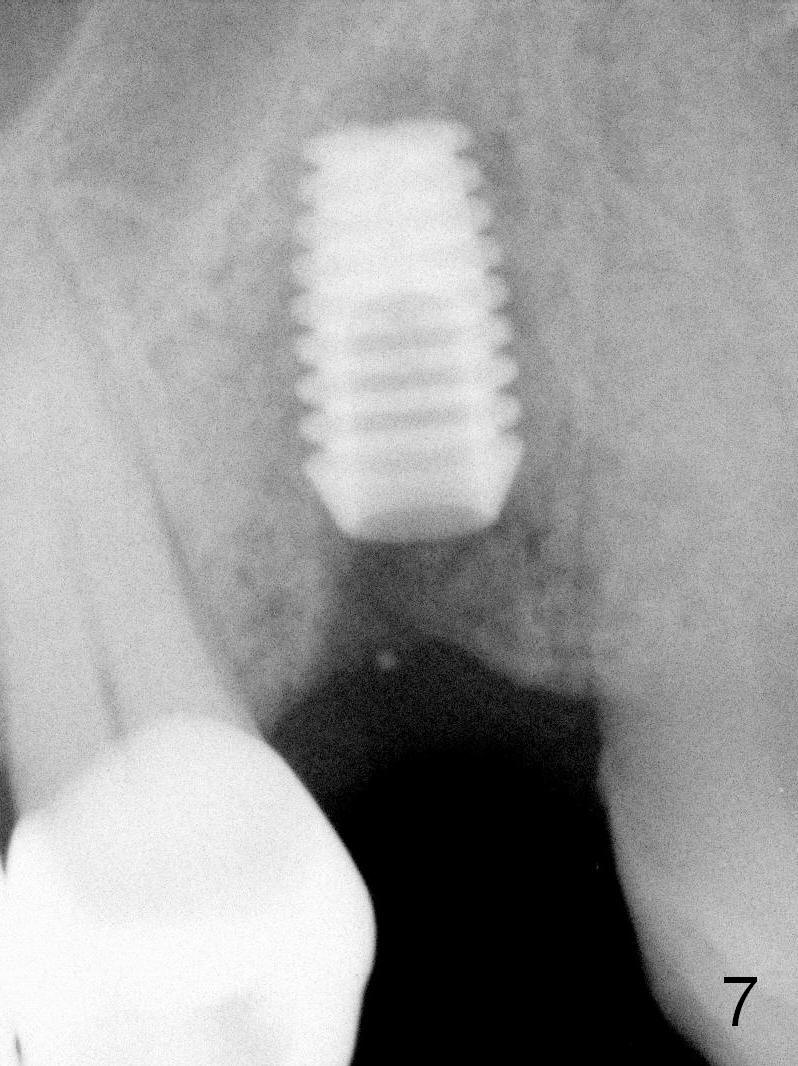

A 68-year-old man has pain and swelling associated with the tooth #5 (Fig.1). The fistula (*) is connected to the periapical radiolucency using a gutta percha (Fig.2 <). There are deep pockets distobuccal and lingual. The lingual root is found to have oblique fracture upon extraction. The distobuccal plate perforates (Fig.3). Collagen plug is placed. The buccal plate is concave (Fig.4) and socket density is low 2.5 months post extraction. Three months post extraction a 4.5x8 mm Bicon implant is placed after reamer and osteotome osteotomy (Fig.6). Bone density around the implant appears to increase 5 months post placement (Fig.7). Porcelain-fused-to-metal crown is cemented 2 weeks later. Bucco-occlusal porcelain chips 2 months post cementation. The patient decides to redo the crown. PA is taken before crown removal (Fig.8: 3 year 10 months post cementation). When a straight abutment is removed (Fig.9 A), a 15° angled abutment has to be used (Fig.10 red) for restoration.